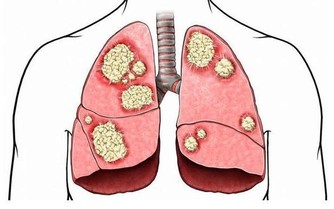

肝臟是人體最大的排毒器官,我們都知道,肝臟一般是不會“喊疼”的,在醫療界看來,肝癌是非常善於隱藏的癌症。

首先,肝臟沒有疼痛細胞,導致癌症已經發生了,疼痛等感覺卻很輕,患者容易被麻痺。此外,肝臟代謝功能很強,即使已經有一部分乾細胞受損了,其他的干細胞會很快進行重新分工,接替它的工作。所以,很多人已經出現了早期肝癌,自己卻不知道。

我們要及時觀察肝臟健康的情況,並做出相應的對策,保證肝臟的健康。